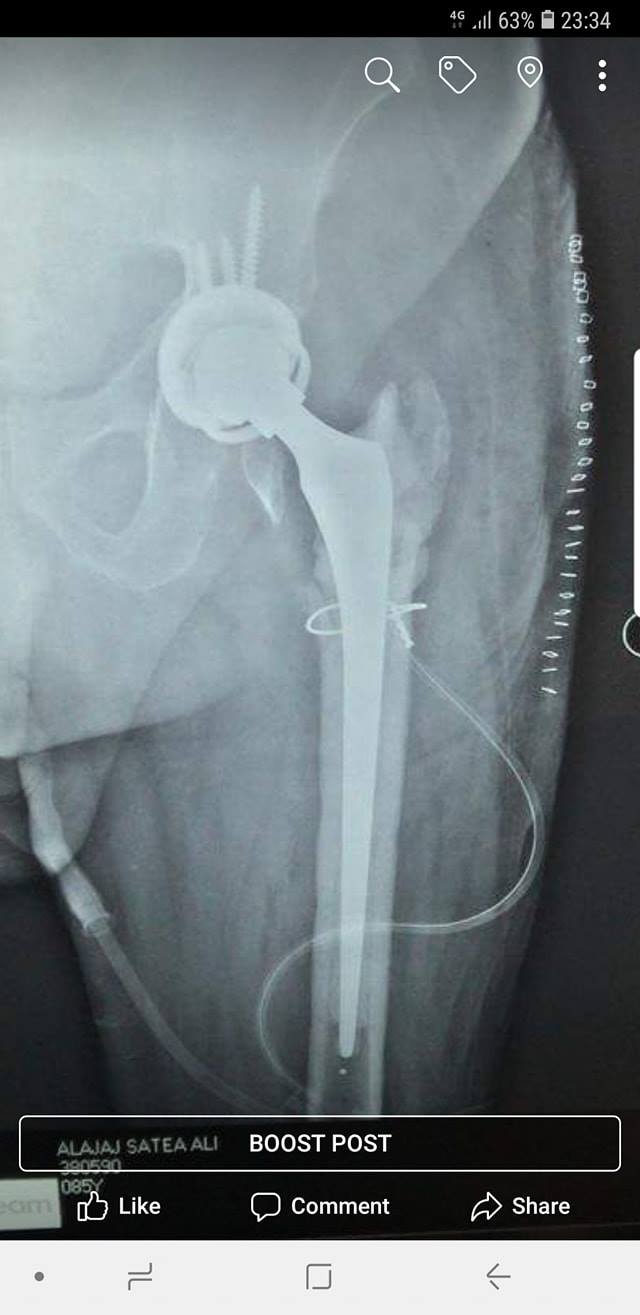

زراعة المفاصل الصناعية ورك و